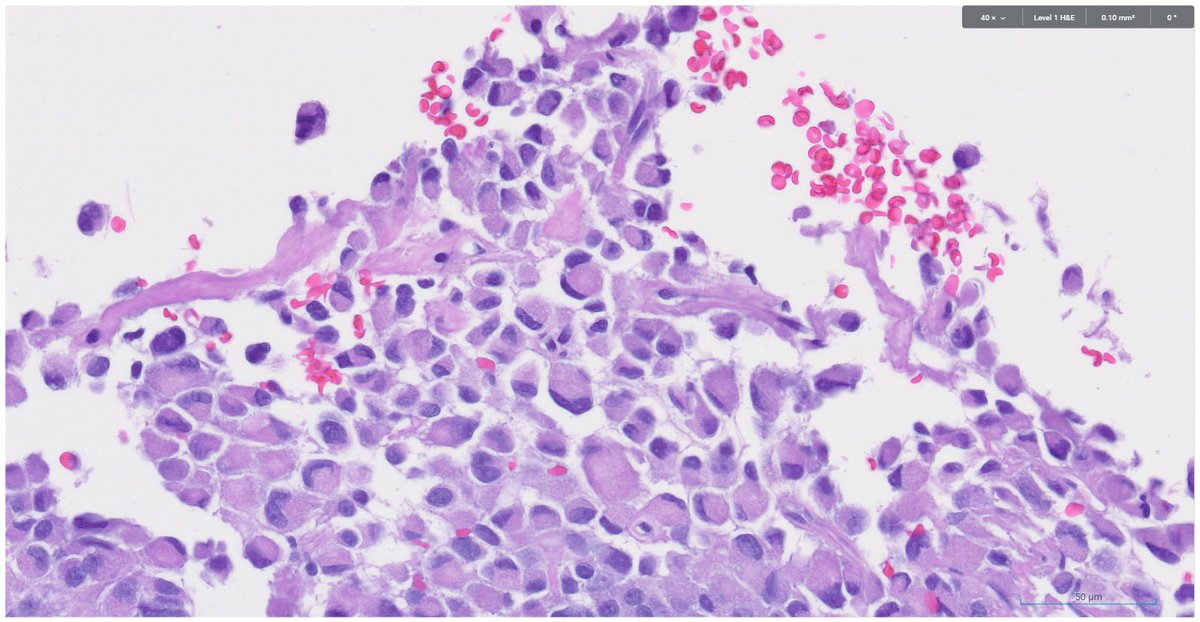

Bread and Butter: It's easy to overlook T4a colorectal carcinoma when mesothelium (indicated) extends up along adipose tissue lobules. In this case, the cancer cells link to the mesothelial cells via inflammation. #umiamipath